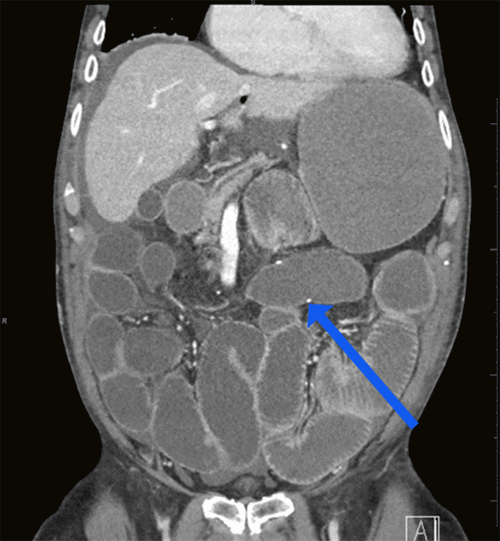

However, on POD 3, he developed concerning symptoms suggestive of small bowel obstruction (SBO), including abdominal distention, diarrhea, nausea, and emesis, necessitating readmission on POD 4. A CT scan of the abdomen and pelvis revealed dilation of the esophagus, stomach, and small bowel, with a patent ileocolic anastomosis and no identifiable transition point (Figure 2). He was managed conservatively for an ileus with nasogastric decompression and bowel rest until POD 6. His abdominal distension and diarrhea resolved, and his diet was advanced. He was discharged on POD 8 on a regular diet, tolerating it well without nausea, vomiting, or distension, and with improving stool consistency. No opioids were administered during this readmission. On POD 10, the patient was readmitted again with nausea, vomiting, and abdominal distension.

Figure 2. Abdominal and Pelvic CT Scan on POD 4. Published with Permission.

Note distended stomach and small bowel loops and a patent ileocolic anastomosis (blue arrow); no evidence of leakage